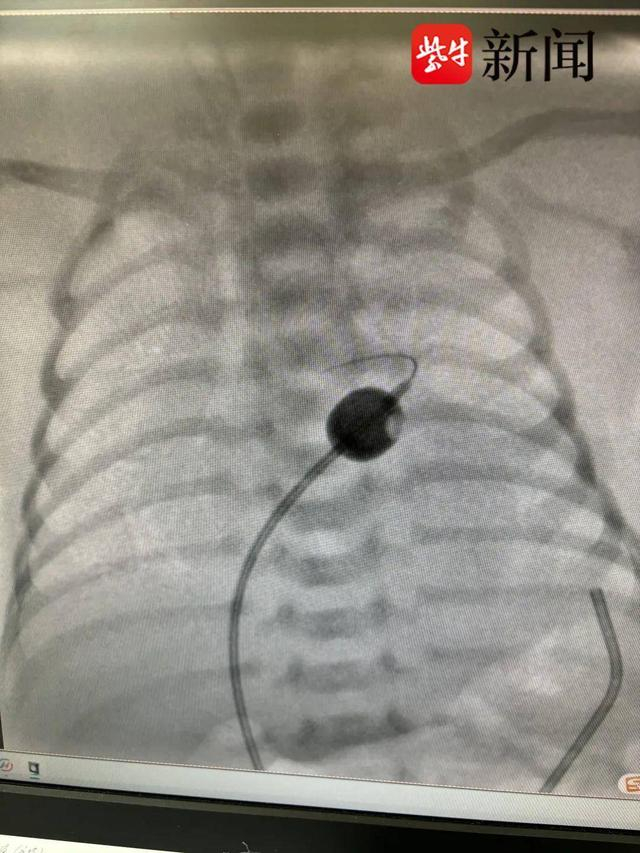

产科安全交接,新生命顺利降临,但早产带来的挑战也随之而来。据了解,该早产儿孕34周,体重仅4斤2两。面对这一紧急情况,苏大附属儿童医院新生儿科和心脏科的专家们迅速行动,为新生儿注射前列地尔药物维持生命通道,并实施气管插管,确保转运过程中的安全。救护车在夜色中飞驰,两小时后,新生儿安全抵达苏州大学附属儿童医院心脏外科重症监护室。在这里,心脏超声检查进一步确认了完全性大动脉转位的诊断。面对新生儿血氧水平不稳和早产低体重的双重挑战,心内科孙凌团队果断进行了经皮球囊房间隔造口术,使新生儿心脏内的血液能够更好地混合流通,为后续的根治手术争取了宝贵的时间。手术效果立竿见影,为这个小生命带来了新生的希望。